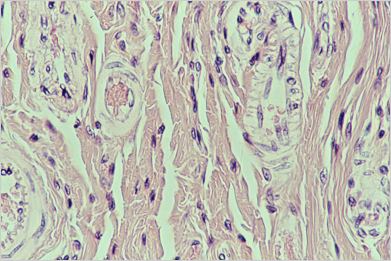

Décollement (diapo 3)